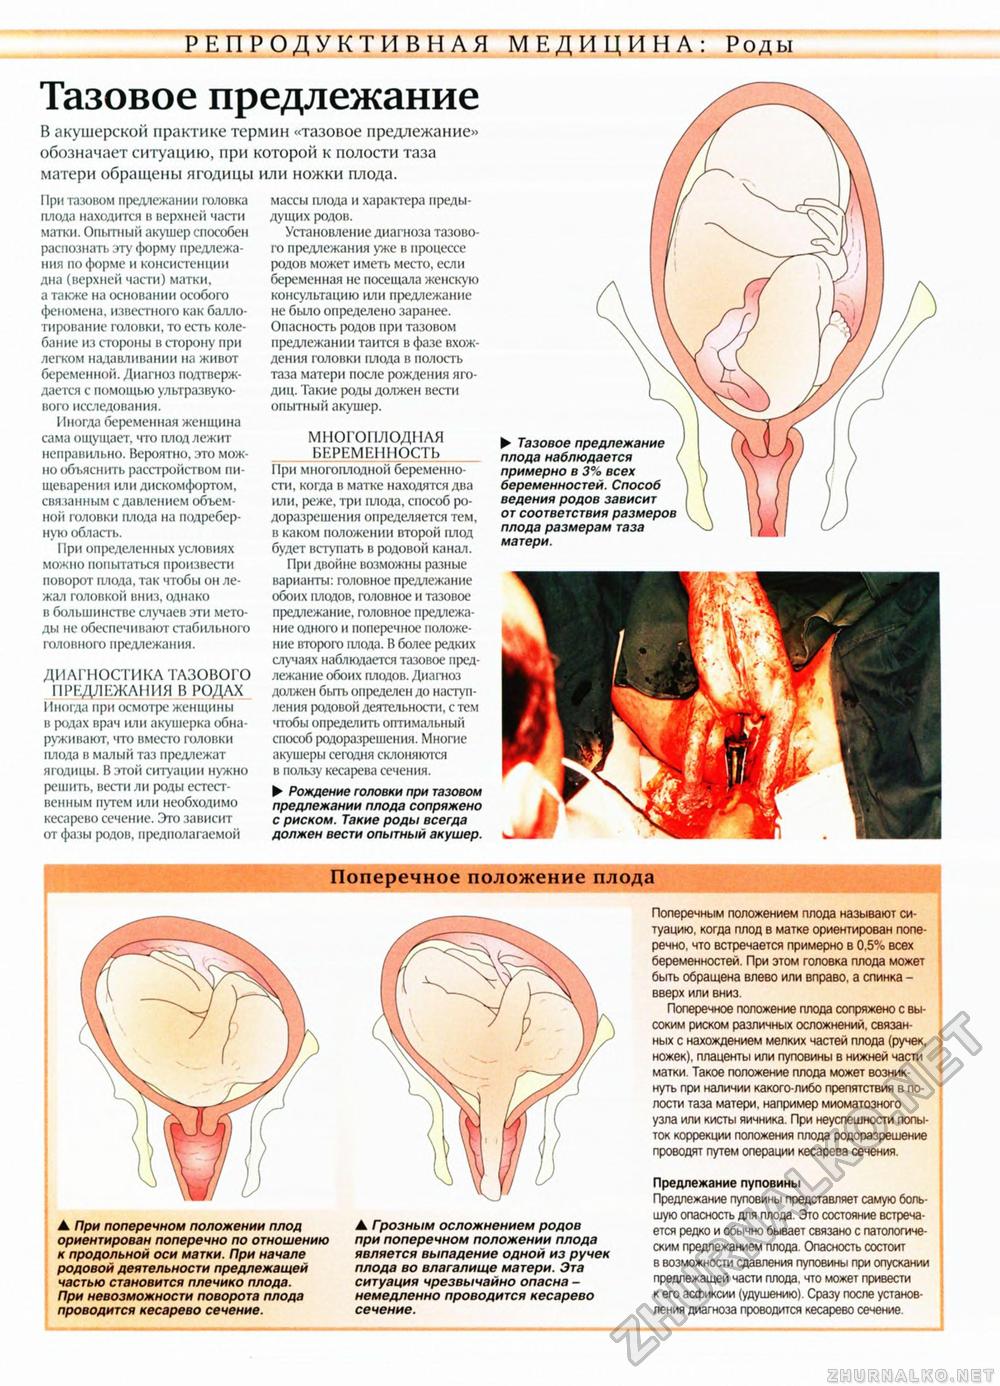

Живот с ягодичным предлежанием

Рождение ребенка в тазовом предлежании